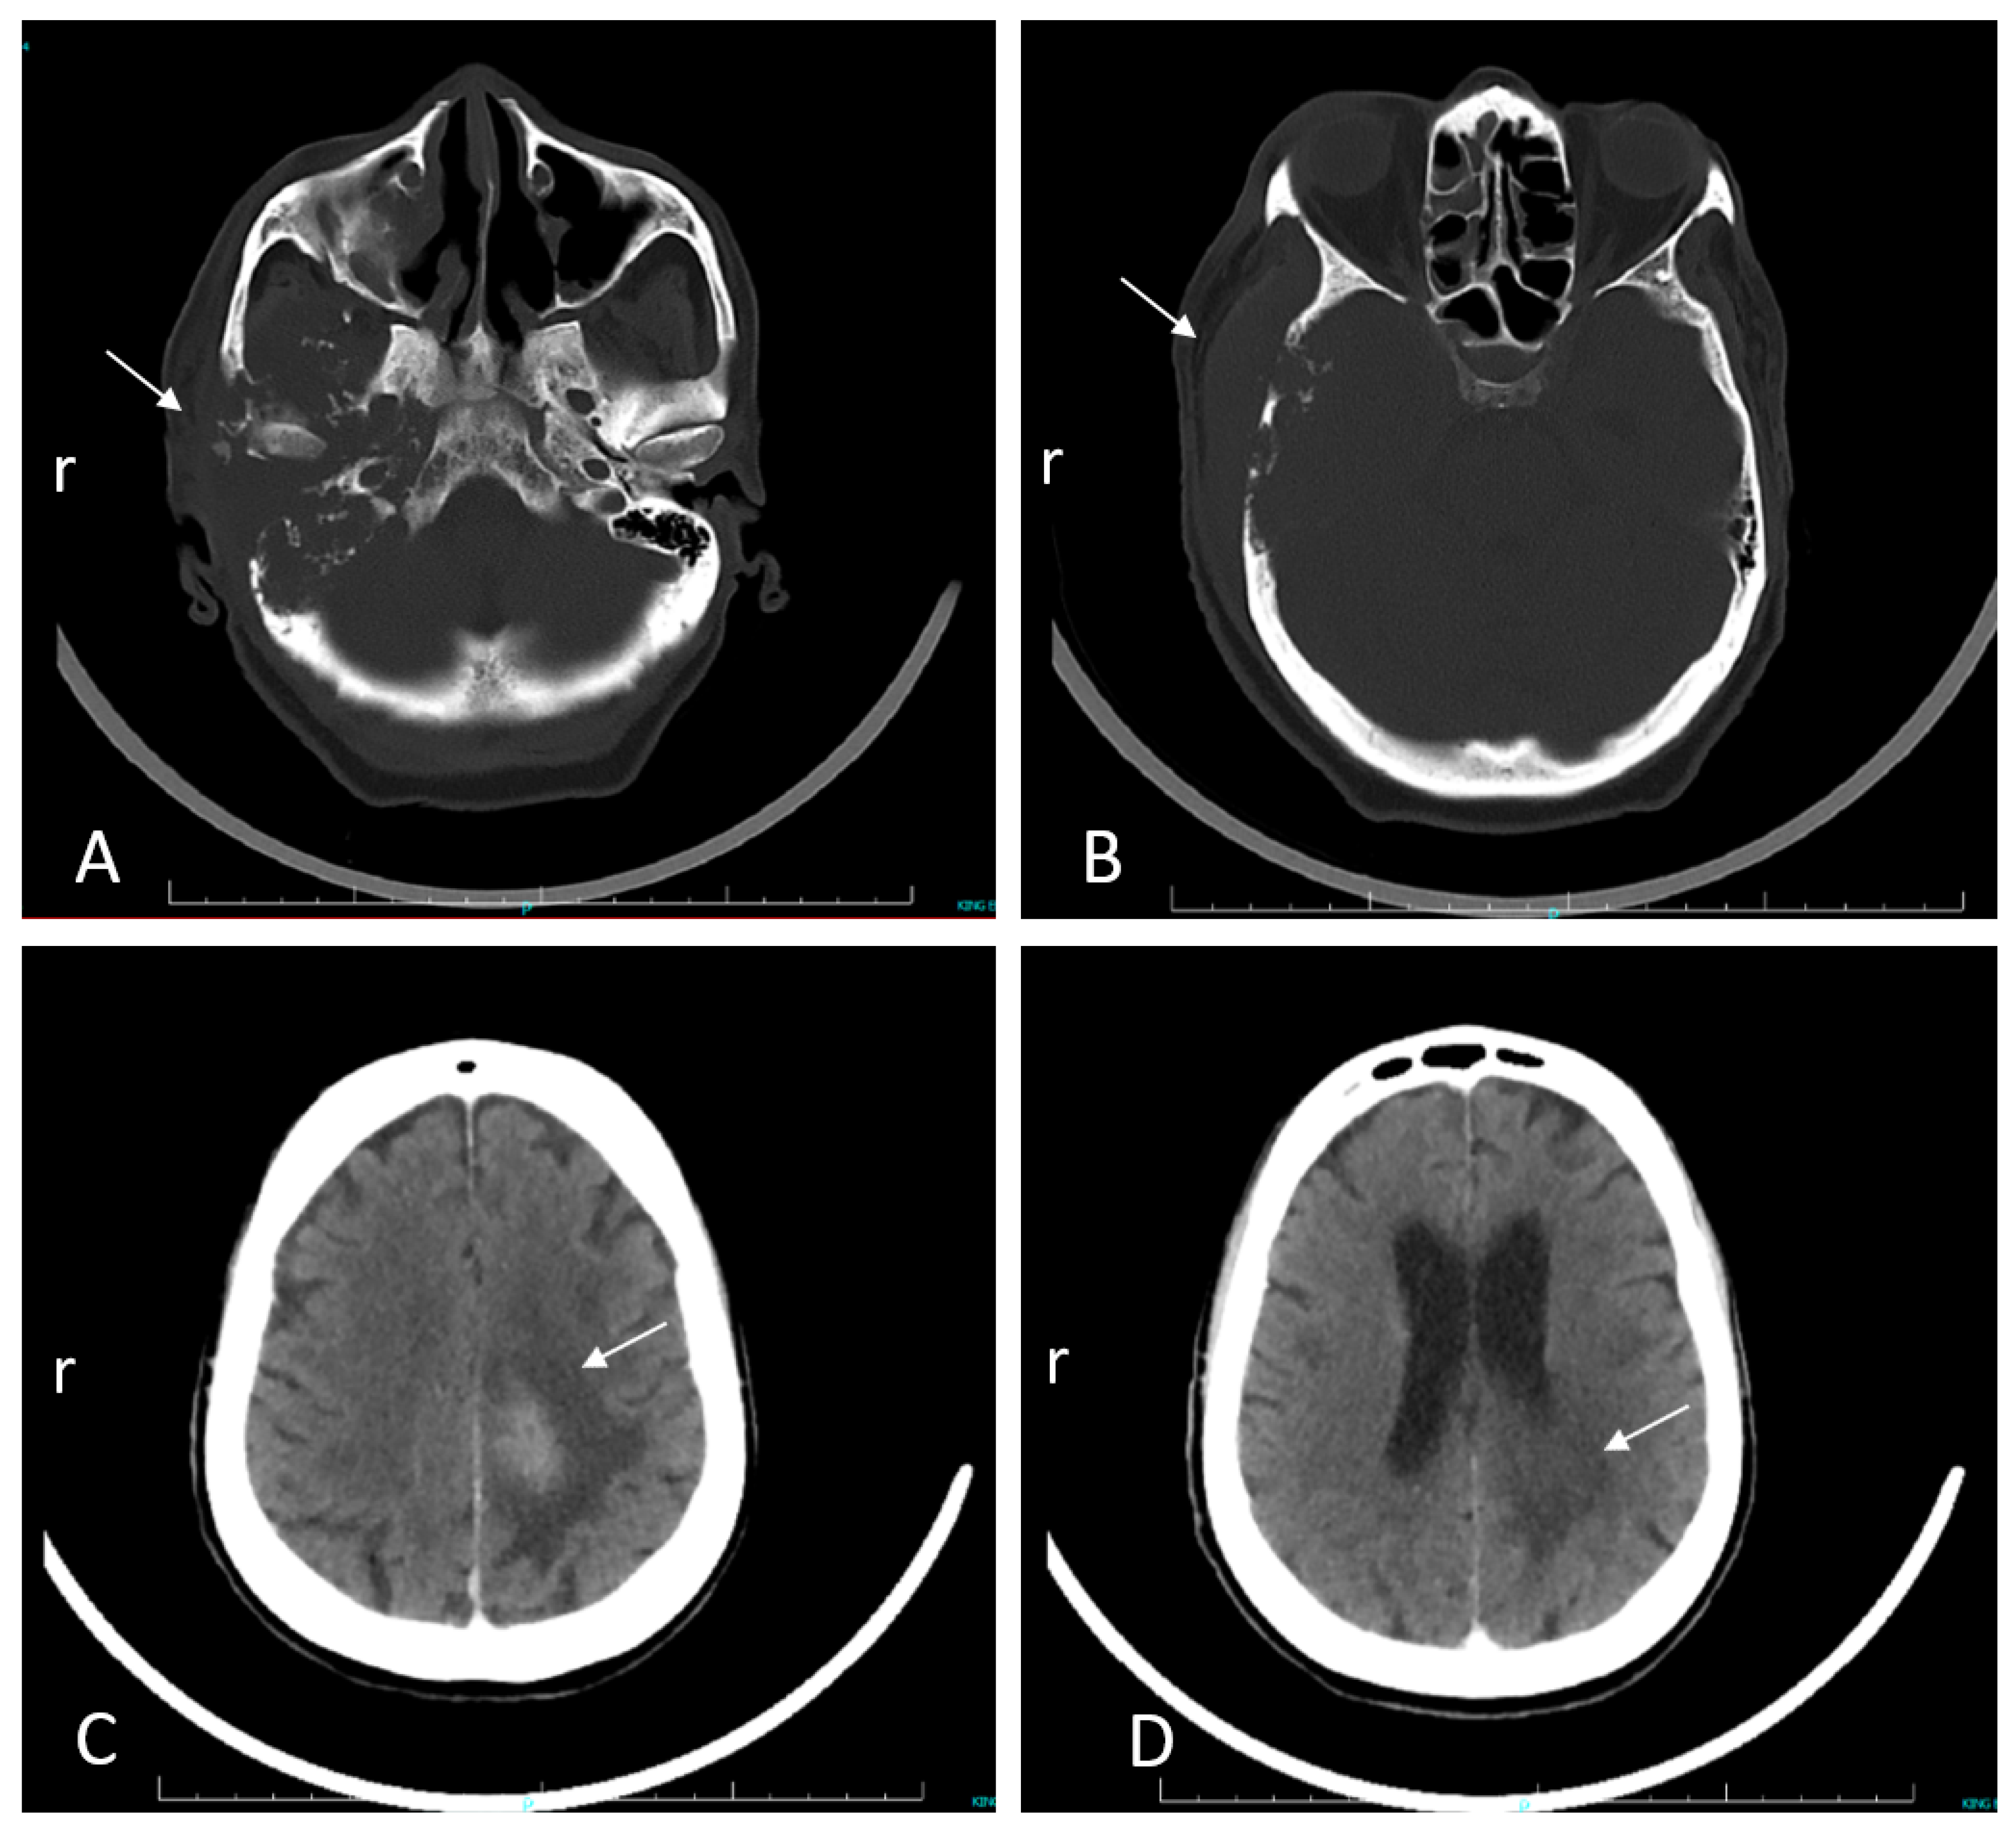

Case Report